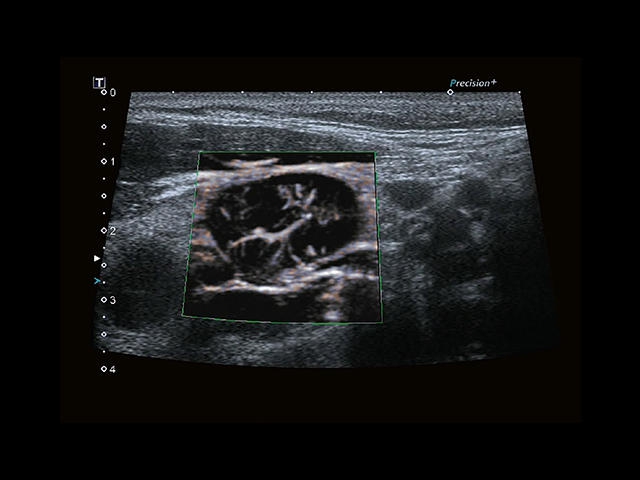

• SMI. Опция, упрощающая визуализацию микроциркуляторного русла. С ее помощью обследуются сосуды с низкой интенсивностью кровотока, изучаются наиболее тонкие структуры. SMI упрощает диагностику новообразований, минимизирует вероятность ошибки.

• MicroPure. Высокотехнологичное решение в области выявления микрокальцификатов – маркеров новообразований злокачественного типа. Маркеры идентифицируются путем изучения затененных изображений целевого участка. Микрокальцификаты отображаются в виде белых пятен.